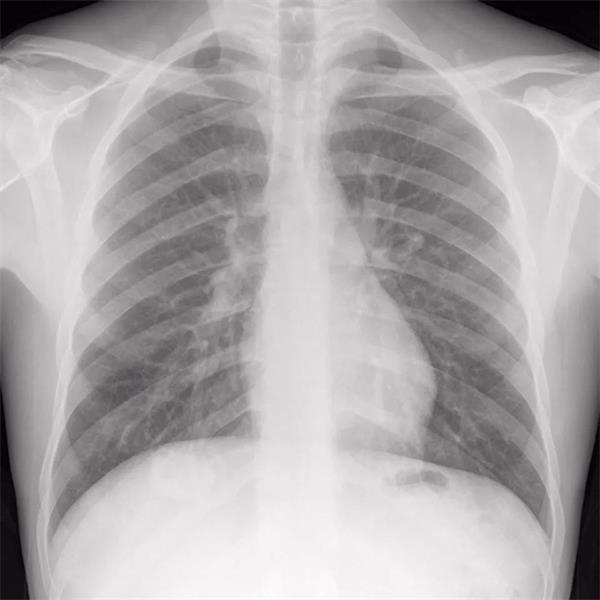

▲ 图为一位成年健康男性的胸部X光片数字化样片,中央处的以及大小正常,且肺部轮廓清晰可辨